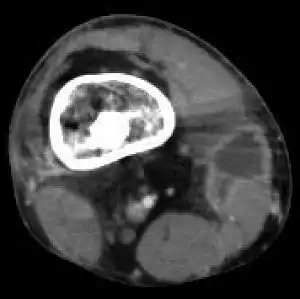

An infectious bone disease is a bone disease primarily associated with an infection.

An example is osteomyelitis.[1]